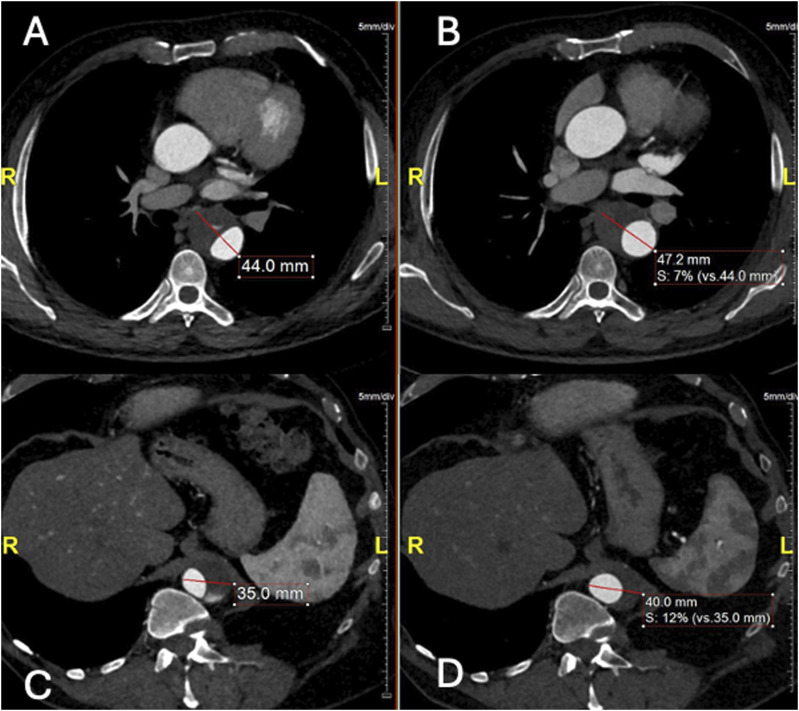

目的:描述在一名接受保守治疗的慢性 B 型主动脉夹层(cTBAD)患者中,采用偏离中心的球囊扩张覆盖支架选择性封堵远端入口撕裂(ET)的技术:一名 63 岁的男性,因慢性 B 型主动脉夹层(cTBAD)接受保守治疗,在随访时出现 FL 部分血栓形成和扩张(胸主动脉 FL 在 6 个月内从 21 mm 增至 27 mm,腹主动脉 FL 在 6 个月内从 11 mm 增至 15 mm)。未发现近端 ET。FL远端灌注是由腹主动脉中的ET造成的,ET为2毫米的肾脏附属动脉(ARA)供血。由于主动脉直径低于血管内修复的阈值,因此计划对远端 ET 和 ARA 进行选择性闭塞。对球囊扩张覆盖支架进行了改良,将覆盖支架向近端偏离中心,使其在穿过 ET 进入 ARA 后形成漏斗状闭塞。为防止术中检测到的膈动脉(PA)可能导致的FL扩张造成Ic型内漏,在改良支架和ARA的管腔内部署了线圈。出院前的计算机断层扫描血管造影显示,ARA和ET均被排除,PA出现了2型内漏:结论:球囊扩张型覆膜支架可通过偏离覆膜支架的中心形成漏斗状来进行改造,以适应不同直径的要求。

PurposeTo describe the technique of off-centering a balloon-expandable covered stent for selective occlusion of a distal entry tear (ET) in a patient, conservatively treated for chronic type B aortic dissection (cTBAD), presenting FL expansion.TechniqueA 63-year-old male, with conservatively managed cTBAD, presented at follow-up with FL partial thrombosis and expansion (thoracic aorta FL from 21 mm to 27 mm and abdominal aorta FL from 11 mm to 15 mm in 6 months). No proximal ET was identifiable. Distal FL perfusion was caused by an ET in the abdominal aorta feeding a 2 mm accessory renal artery (ARA). As the aortic diameter was below the threshold for endovascular repair, a selective occlusion of the distal ET and ARA was planned. A balloon-expandable covered stent was modified by off-centering the covered stent proximally and resulting in a funnel-shape occluder after deployment across the ET into the ARA. To prevent type Ic endoleak due to possible FL expansion caused by an intra-operatively detected phrenic artery (PA), coils were deployed into the lumen of the modified stent and the ARA. The pre-discharge computed tomography angiography showed exclusion of both the ARA and ET and a type 2 endoleak from the PA.ConclusionA balloon-expandable covered stent can be modified by off-centering the covered stent resulting in a funnel shape to adapt to different diameter requirements.